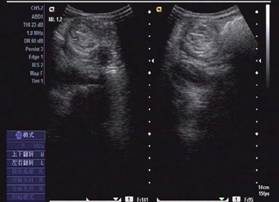

圖示:該患兒當(dāng)時(shí)聲像圖表現(xiàn)

超聲圖像表現(xiàn)

1、腸套疊部位顯示邊界清楚的包塊。其橫斷面呈大環(huán)套小環(huán)的特征性表現(xiàn),即“同心圓征”或“靶環(huán)征”。外圓呈均勻的低回聲環(huán)帶,系鞘部腸壁回聲,低回聲帶系水腫增厚的反折壁及其與鞘部之間的少量腸內(nèi)液體形成。在大的外圓內(nèi),又有一個(gè)小低回聲環(huán)帶,形成內(nèi)圓。內(nèi)、外圓間為高回聲環(huán),中心部為高回聲團(tuán),其邊緣欠光整。套疊部的縱斷面呈“套筒征”或“假腎征”。有時(shí)可能顯示套疊的頂部和頸部,頂部呈指頭狀盲端?!凹倌I征”通常是在套疊時(shí)間較長,腸壁發(fā)生嚴(yán)重水腫時(shí)出現(xiàn),或是成人患者存在腸管腫瘤或息肉時(shí)出現(xiàn)。